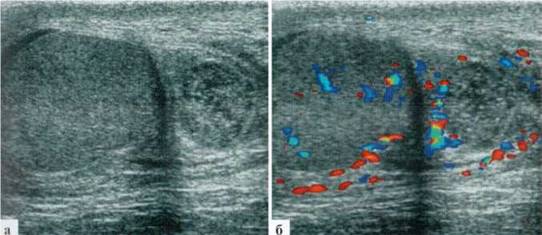

В редких случаях диаметр измененной гидатиты может превышать 10—12 мм и у маленьких детей практически достигать размеров яичка (рис. 2.1.2).

Рис. 2.1.2. Крупные размеры трансформированной гидатиды: 1 — яичко, 2 — гидатида. Размеры яичка и гидатиды практически одинаковы. Сосудистый рисунок при ДДС в гидатиде не прослеживается (б)